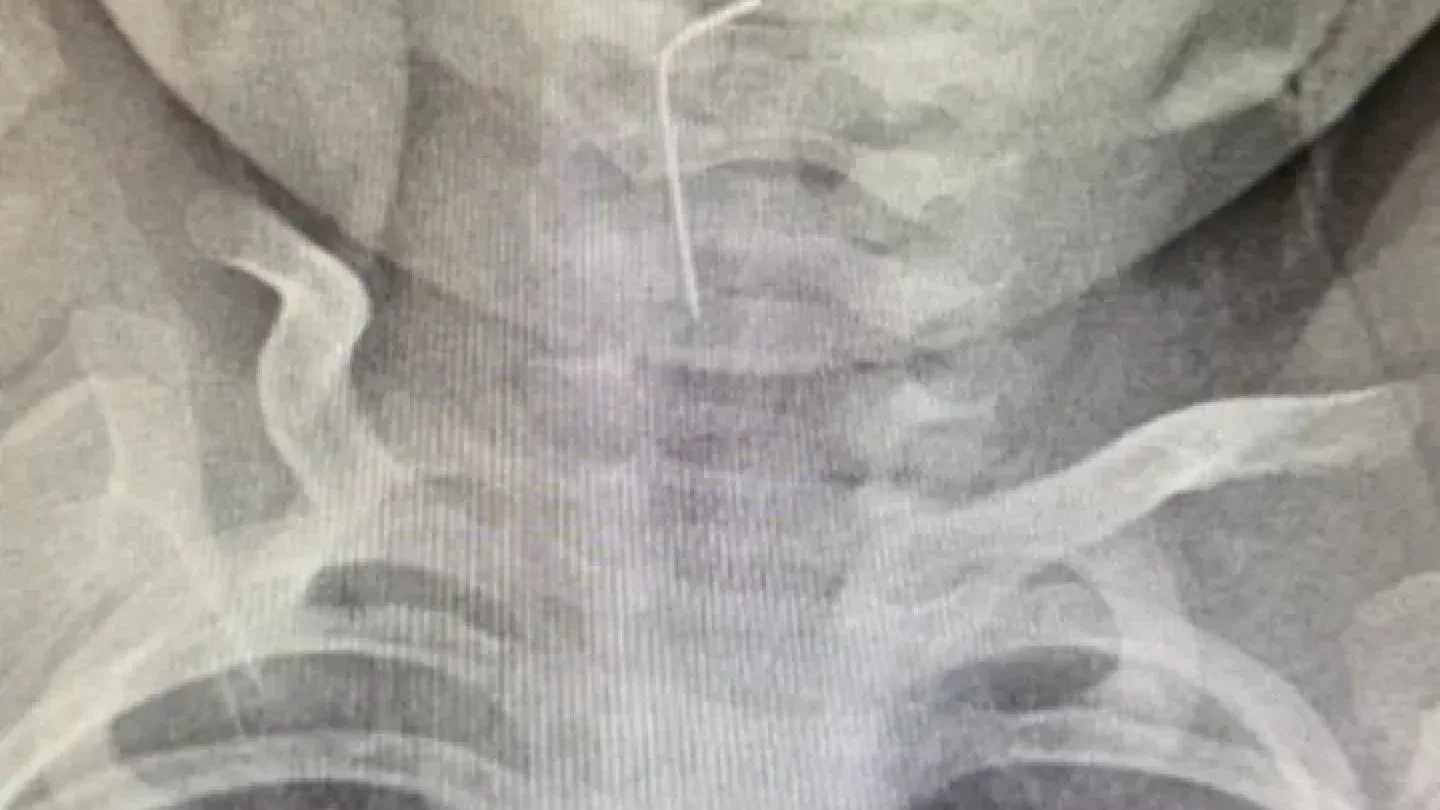

Түркістан облыстық балалар ауруханасына 9 айлық сәби жедел жәрдеммен шұғыл жеткізілді. Сәби абайсызда ине жұтып қойған, деп хабарлайды Orda.kz «Qazaqstan» ұлттық телеарнасына сілтеп.

Дәрігерлер рентгендік тексеру арқылы бөгде заттың орналасқан орнын анықтап, дереу эндоскопиялық әдіспен оны сәтті алып шықты.

Анықталғандай, сәби абайсызда ине жұтып қойған. Дәрігерлер дереу рентгенологиялық тексеру жүргізіп, бөгде заттың нақты орналасқан орнын анықтаған.

Түркістан облыстық балалар ауруханасының мамандары – хирург Мұқағали Темірбеков пен эндоскопист Бабыр Ырысқұлов өңеште тұрып қалған бөгде затты сәтті алып шыққан.